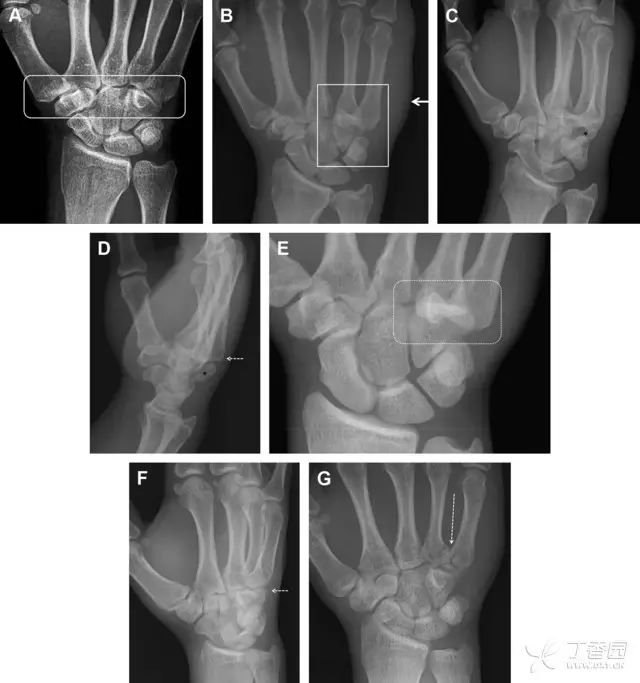

常规进行前后位、侧位、斜位 X 线检查,对于大多数桡骨远端骨折来说不容易漏诊;但是对于无移位的骨折,特别是桡骨茎突骨折,容易漏诊。桡骨茎突骨折是一斜行的骨折,常累及关节面,常发生于轴向应力或直接打击。

图 1 57 岁女性,摔倒后手掌撑地,桡骨茎突压痛。(A~C)前后位、斜位、侧位片示软组织肿胀(*)和发丝样骨折(白色箭头);(D~F)2 周后,前后位、斜位、侧位片示骨折线显明,由于新骨痂沉积而呈现透亮线与硬化线并存;(G~I)另一患者,桡骨茎突骨折在前后位及侧位片上显示不明显,而在斜位片显示更清楚

舟状骨骨折 60%~70% 发生于腰部,15% 发生于近极, 10% 发生于远极, 8% 发生于远端关节面。除了常规的前后位、侧位、斜位片外,还需要拍专门的舟状骨位片(腕关节尺偏,以舟状骨为中心的腕关节前后位片),特别是鼻烟壶有压痛时。

图 2 舟状骨骨折 (A、B)第 1 例患者,舟状骨远极关节内骨折(白色箭头),斜位片显示较清楚(B);(C、D)第 2 例患者,舟状骨腰部骨折(虚线箭头),斜位片显示较清楚(D);(E~H)第 3 例患者,舟状骨近极骨折,常规 X 线片均未看到骨折,而在舟状骨位片上才能见到骨折(虚线圆)

掌板是掌指关节和指间关节关节囊掌侧的纤维结构,防止关节过伸。掌板的远端部是增厚的纤维软骨,附着于指骨掌侧基底部,而其两侧与侧副韧带的纤维融合。掌板骨折多发生于过伸损伤,为撕脱性骨折。

图 3 掌板骨折(A~C)小指前后位、斜位、侧位片,由于骨折的部位及特点,在前后位片上通常难以发现骨折;放大后的斜位(D)、侧位(E)可见一骨碎片(白色箭头)

腕掌关节骨折脱位为高能量损伤,常伴有神经损伤。腕掌关节组成骨多,侧位片上重叠遮挡多,骨折不易发现,容易漏诊。在前后位片上,关节面不平滑、关节间隙不对称、关节皮质破坏、关节面重叠常提示腕掌关节骨折脱位。特别是第 4、5 腕掌关节脱位,在前后位片上不容易发现;该损伤不稳定,也称为「变异型拳击手损伤/骨折」。

图 4 第 4、5 腕掌关节骨折脱位。(A)正常腕掌关节,关节面平衡起伏、平行;前后位(B)、斜位(C)、侧位(D),第 5 掌骨近端附近软组织肿胀(白色箭头),冠状面关节面重叠,背侧撞击剪切应力致钩状骨骨折(*),在前后位及斜位片上可见双密度影。第 4 掌骨底部可见微小骨折碎片(D,虚线箭头),第 4、5 掌骨掌侧成角。(E~G)变异型拳击手损伤:第 4、5 掌骨背侧脱位而未见骨折(E,虚线方框),钩状骨有骨折小碎片(F,短虚线箭头),第 4 掌骨基底部关节内骨折(G,长虚线箭头)

钩状骨骨折可发生于体部和钩部,钩部骨折更多见,可合并有第 4、5 腕掌关节脱位。受伤机制由直接暴力或腕横韧带撕脱伤所致。骨折征象包括钩部无显示、骨皮质边缘模糊、硬化或双密度影等。常规的正侧位常无法明确诊断,需要加拍腕管位,可清晰显示其钩部。

图 5 打高尔夫球后腕部急性疼痛。常规腕关节 X 线片正常(X)。腕管位片(B)隐约可见钩部横行骨折(虚线箭头),CT 检查(C、D)进一步明确了诊断

三角骨骨折是除舟状骨骨折外腕关节常见的骨折之一。其背侧是背侧桡腕韧带的附着点,因此背侧骨折更常见。常规正侧位片基本可明确诊断。背侧骨折可在侧位片上看到一小骨块。

图 6 三角骨骨折。(A)前后位片骨折不明显,(B)仅在侧位片上见一小骨块(短箭头),伴有软组织肿胀(长箭头)。